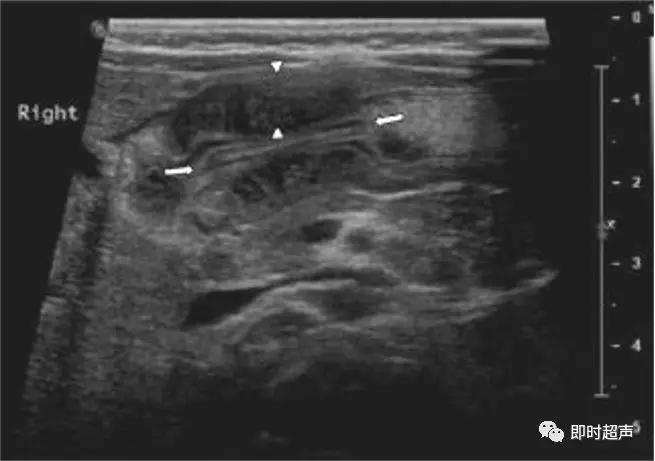

肠套叠超声表现

短轴切面同心圆征

长轴切面套筒征、短轴切面同心圆征